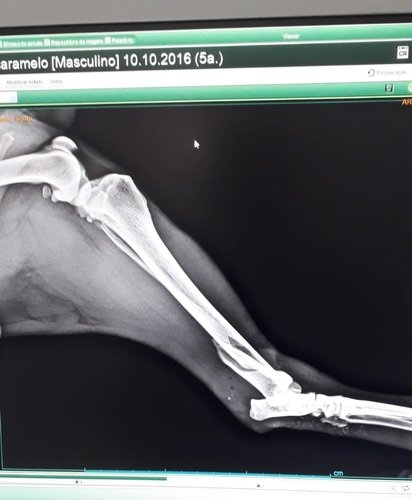

Radiografias antes